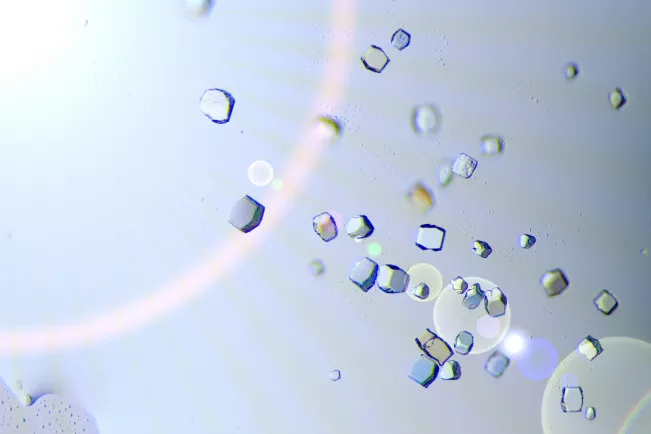

Das Ministerium für Kultur und Wissenschaft des Landes Nordrhein-Westfalen fördert dieses Projekt im Rahmen des Förderprogramms Fokus Forschung an Hochschulen für angewandte Wissenschaften - Geräte. Der geförderte Kristallisationsroboter soll die atomare Strukturaufklärung von Biomolekülen im Kontext von Gesundheitsforschung an der H-BRS ausbauen und bestehende Forschungsvorhaben in den Instituten für Funktionale Gen-Analytik (IFGA), sowie Technik, Ressourcenschonung und Energieeffizienz (TREE) erweitern. Die Strukturaufklärung mittels biomolekularer Röntgenkristallographie erlaubt detaillierte Einsichten in zelluläre Architektur und Prozesse. Unterschiedlichste Systeme, einschließlich Proteinen, DNA, RNA, biologische Komplexe und Protein-Ligand-Komplexe, können über das Gerät wirkungsvoll und ressourcenschonend kristallisiert werden und sind damit für die atomare Strukturaufklärung zugänglich. In Verbindung mit einem am Standort verfügbaren µ-Fokus-Röntgendiffraktometer und umfangreicher Analysetechniken, steht eine effiziente Pipeline für Struktur-Funktions-Studien zur Verfügung, die in Kooperationsprojekten mit akademischen und industriellen Partnern eingesetzt wird. Der Kristallisationsroboter wird primär in Forschungsprojekten zur grundlagenorientierten Entschlüsselung molekularer Krankheitsmechanismen, sowie zur anwendungsorientierten strukturbasierten Wirkstoffentwicklung eingesetzt werden. Damit sollen neue Erkenntnisse zum Verständnis und der Modulation Akuter Myeloischer Leukämie und Glioblastomen, sowie motorprotein-assoziierter Krankheiten